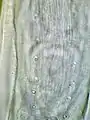

Serpentine path of Gongylonema pulchrum in the lip mucosa of a man [1]

These are all pictures from a single Gongylonema pulchrum male extracted from a man in France.[1]